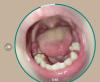

Стоматит лечат антибиотиками? Советы мам по лечению

Стоматит лечат антибиотиками??

Буквально 2-3 язвы